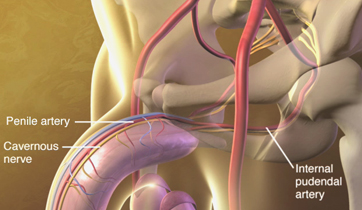

Erectile Dysfunction

Medtronic Corporation

This animationis intended to explain Erectile Dysfunction to physicians. It shows the vessels and nerves involved in blood flow obstruction to the penis, and the erectile tissue's failure to enlarge. The animation also suggests the benefits of clearing the obstruction by using stents.